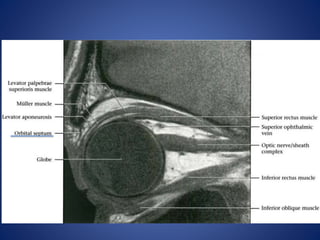

• #37 Orbital septum separates preseptal space from orbit. Orbital septum is a connective tissue extension of periosteum reflected into upper and lower eyelids. It serves as a barrier to spread of infection to the orbit.